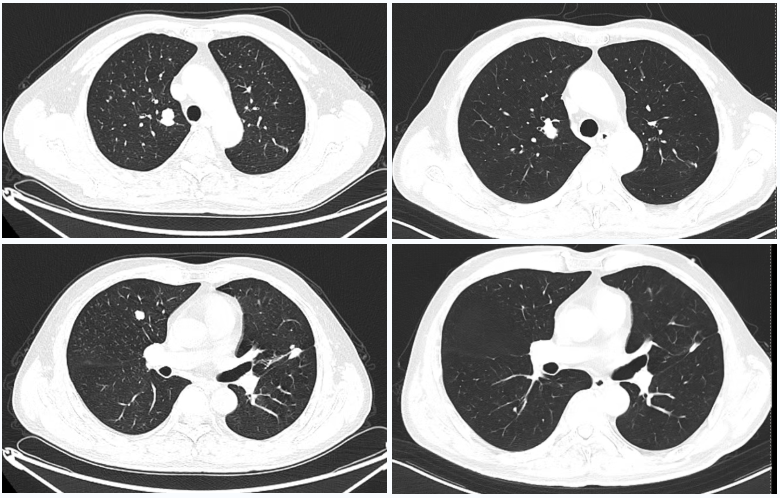

△2025年8月疗效评估时患者CT检查(右)较基线(左)对比

△2023年2月患者基线时CT(左)与2024年4月时CT(右)检查所见对比